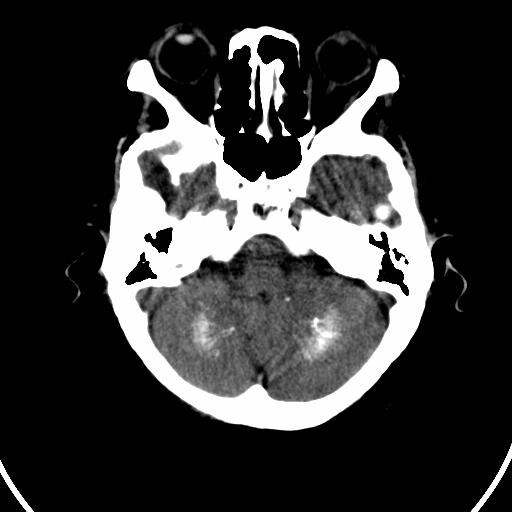

今天碰到的病人,发图上来,大家帮看看该如何诊断?

双侧小脑齿状核钙化,患者是成年人就无病理意义。

双侧小脑齿状核钙化

双侧小脑齿状核钙化,生理性钙化

考虑甲状旁腺功能低下

双侧小脑齿状核钙化 ,原因挺多,有生理性也有病理性的